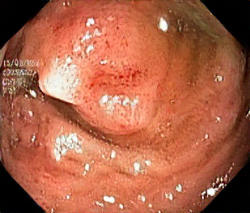

A few sample images and the corresponding masks of the polyp dataset in HyperKvasir are shown in Fig 2. The polyp images are RGB images. The masks of the polyp images are single-channel images with white () for true pixels, which represent polyp regions, and black () for false pixels, which represent clean colon or background regions. In this dataset, there are different sizes of polyps. The distribution of polyp sizes as a percentage of the full image size is presented in the histogram plot in Fig 3, and we can observe that there are more relatively small polyps compared to larger polyps. Additionally, a subset of this dataset was used to prove that the performance of segmentation models trained with small datasets can be improved using our SinGAN-Seg pipeline, and the whole dataset was used to show the effect of using SinGAN-Seg generated synthetic images instead of a large dataset which has enough data to train segmentation models. In this regard, this dataset was used for two purposes:

After training SinGAN-Seg models, we generated random samples per real image using the input scale , which is the lowest scale that uses a random noise input instead of a re-scaled input image. For more details about these scaling numbers and corresponding output behaviors, please refer to the vanilla SinGAN paper [56]. Three randomly selected training images and the corresponding first synthetic images generated using scale are depicted in Fig 4. The first column of the figure represents the real images and the ground truth mask annotated from experts. The rest of the columns represent randomly generated synthetic images and the corresponding generated mask.